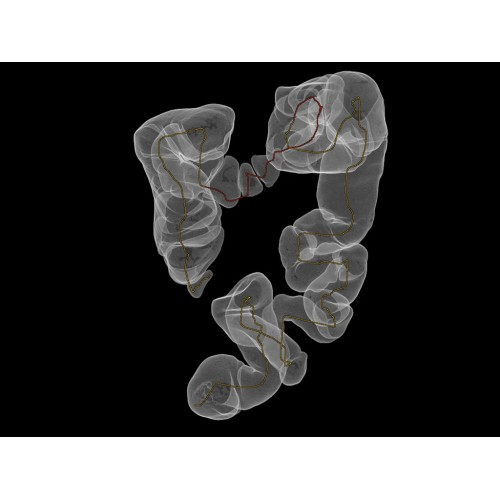

Позволяет проводить комплексные исследования всех анатомических зон, включая нейровизуализацию, ангиографию, исследования органов грудной и брюшной полости. Особенно эффективен для раннего выявления онкологических заболеваний.